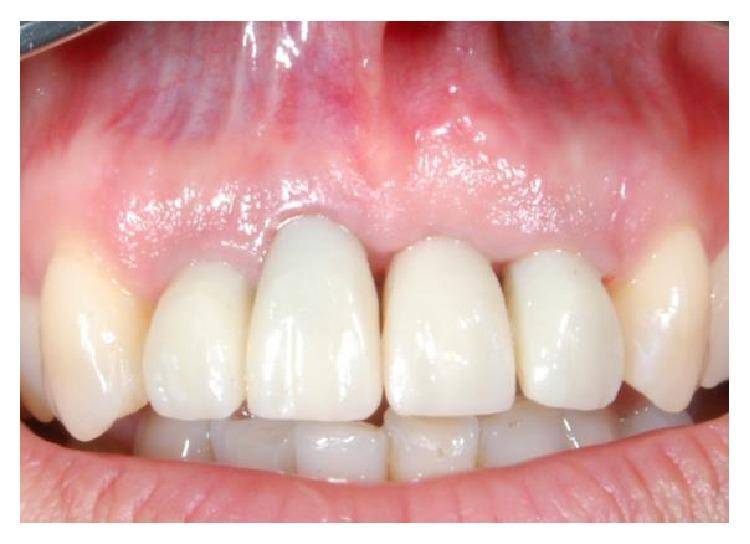

The functional and aesthetic restoration of teeth compromised due to aggressive periodontitis presents numerous challenges for the clinician. Horizontal bone loss and soft tissue destruction resulting from periodontitis can impede implant placement and the regeneration of an aesthetically pleasing gingival smile line, often requiring bone augmentation and mucogingival surgery, respectively. Conservative approaches to the treatment of aggressive periodontitis (i.e., treatments that use minimally invasive tools and techniques) have been purported to yield positive outcomes. Here, we report on the treatment and five-year follow-up of patient suffering from aggressive periodontitis using a minimally invasive surgical technique and implant system. By using the methods described herein, we were able to achieve the immediate aesthetic and functional restoration of the maxillary incisors in a case that would otherwise require bone augmentation and extensive mucogingival surgery. This technique represents a conservative and efficacious alternative to the aesthetic and functional replacement of teeth compromised due to aggressive periodontitis.

侵袭性牙周炎导致牙齿功能和美观受损,给临床医生带来诸多挑战。牙周炎引起的水平骨吸收和软组织破坏会妨碍种植体植入以及美观的牙龈微笑线的再生,通常分别需要进行骨增量和膜龈手术。据称,侵袭性牙周炎的保守治疗方法(即使用微创工具和技术的治疗方法)能产生积极效果。在此,我们报告了一名侵袭性牙周炎患者采用微创外科技术和种植系统的治疗及五年随访情况。通过使用本文所述方法,在原本需要骨增量和广泛膜龈手术的病例中,我们成功实现了上颌切牙的即刻美观和功能恢复。该技术是侵袭性牙周炎导致牙齿功能和美观受损时,一种保守且有效的替代治疗方法。